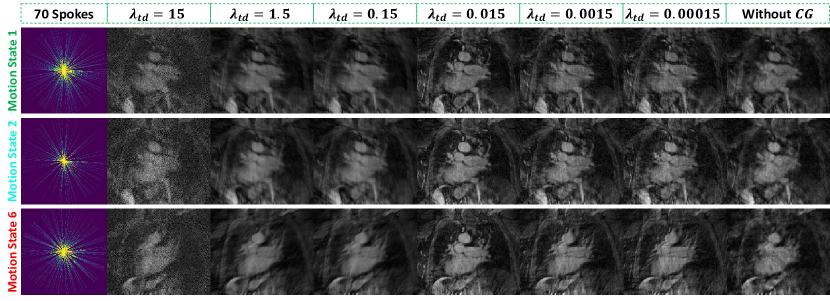

Figure 7 presents a qualitative comparison of lung reconstructions with 70, 35, and 17 spokes across motion states using Zero-filled, XD-GRASP, and the proposed dDiMo method. Reconstructions are shown for representative motion states (Motion State 1, Motion State 2, and Motion State 6), highlighting the effectiveness of each method in handling undersampled dynamic lung imaging. Zero-filled reconstructions exhibit severe artifacts and significant loss of structural detail, particularly in motion-affected regions. For instance, Motion State 1 demonstrates extensive blurring and cannot delineate key anatomical features. XD-GRASP reduces artifacts and partially restores structural details compared to Zero-filled; however, residual blurring, missing subtle textures, and noise remain apparent, especially at higher undersampling levels (e.g., 17 spokes). In contrast, dDiMo achieves superior performance across all motion states by effectively suppressing artifacts, recovering fine structural details, and maintaining consistency across motion states. In the most challenging scenario, with 17 spokes, dDiMo reconstructs most of the structural details, producing sharper boundaries and enhanced structural integrity across respiratory phases. These qualitative results highlight the advantages of the proposed dDiMo method over traditional approaches, demonstrating its capacity to restore structural details and improve motion-resolved reconstructions.

Quantitative results comparing reconstruction methods at different undersampling levels (70, 35, and 17 spokes) are summarized in Table 2. dDiMo consistently achieves the highest PSNR and overall image similarity with respect to the reference across all undersampling levels, outperforming both Zero-filled and XD-GRASP. While XD-GRASP achieves the highest Tenengrad score at all undersampling levels, it performs worse in terms of overall image similarity. This is attributed to the presence of noise in XD-GRASP reconstructions, which leads to inflated Tenengrad scores, as also observed in Figure 7. Violin plots in Figure 8 provide a visual comparison of the distributions of PSNR, SSIM, NMSE, and Tenengrad metrics for different acceleration settings. dDiMo exhibits narrower distributions and fewer outliers compared to Zero-filled and XD-GRASP in most cases, reflecting its stable and robust performance.

The ablation study evaluated the effectiveness of the proposed temporal guidance priors, including - and - priors, by analyzing results with different weighting factors and from Eq. (22) on cardiac cine data, as presented in Supporting Information Figure S3. The influence of the number of reverse diffusion steps on reconstruction fidelity and computational runtime was analyzed on cardiac cine data, as depicted in Supporting Information Figure S4. Additionally, the impact of incorporating the CG module during inference was assessed on dynamic lung data, with results shown in Supporting Information Figure S5.

Incorporating - and - regularization—derived directly from time-resolved data provides valuable guidance during the diffusion process. This approach ensures accurate temporal alignment and enhances the recovery of fine image details, as is shown by comparing dDiMo with other competitive methods with (e.g., CRNN) or without (e.g., DiMo) temporal characterization. Also, it was highlighted in the ablation study results (Supporting Information Figure S3) that the reconstruction performance of the - prior improves significantly as its weighting factor increases, with optimal results achieved at . A similar trend is observed for the - prior, with the performance increasing when the weighting factors increase to 1. This illustrates the contribution of - and - regularization to improving reconstruction performance in the cardiac cine data. However, notably, the performance wasn’t further improved with a higher - and - weight, indicating optimal performance exists with dataset-specific tunning of those numbers. While not shown in the result, we realized the result for the golden-angle radial lung data relies more on the - component rather than the - characterization, as we used a relatively small weight 0.001 for - component. This is mainly because the learning of the accurate - priors in the center ACS region of radial k-space is extremely challenging and prone to error due to the highly oversampled k-space center and small ACS coverage, especially at extremely few radial spokes (e.g., 35 or 17 spokes at Figure 7) [63]. The CG layer also plays an important role in enhancing performance within this framework. Supporting Information Figure S4 illustrates that while dDiMo without CG can recover a substantial amount of image structure from undersampled data, it often results in less clear images. By implementing temporal sparsity through CG optimization, sharper reconstructions with finer details are achieved as the weighting factor in Eq. (20) increases. In the lung dataset, the optimal value for was found to be 0.015. Higher values led to degraded reconstructions, which were characterized by noise and blurring. Nevertheless, we demonstrate the inclusion of - and - priors and CG into the diffusion modeling can be beneficial to characterize dynamic information in dynamic MRI reconstruction; care has to be cast to carefully leverage the good aspects of those modules. As with many dedicated deep learning algorithms with fine structures and components, hyperparameter tuning is never trivial and forgiven, including for dDiMo. Further research is warranted to explore robust, cost-effective, and hopefully automatic ways to facilitate this process [64].

Figure S5. Results of the ablation study validating the effectiveness of the conjugate gradient (CG) module in dDiMo during inference on continuously acquired golden-angle radial multicoil free-breathing lung data with 70 spokes. The study evaluates the impact of varying the weighting factor in the objective function, which regulates the temporal finite difference constraint to enforce temporal sparsity. Tested values range from 15 to 0.00015, including a condition where the CG module is excluded. Representative results are shown for Motion States 1, 2, and 6. The findings indicate that yields the best results across motion states, producing sharper images with finer details. Larger or smaller values, as well as excluding the CG module, result in blurrier and noisier reconstructions. For the experiments presented in the main manuscript, was chosen to achieve an optimal trade-off between image quality and inference time efficiency.